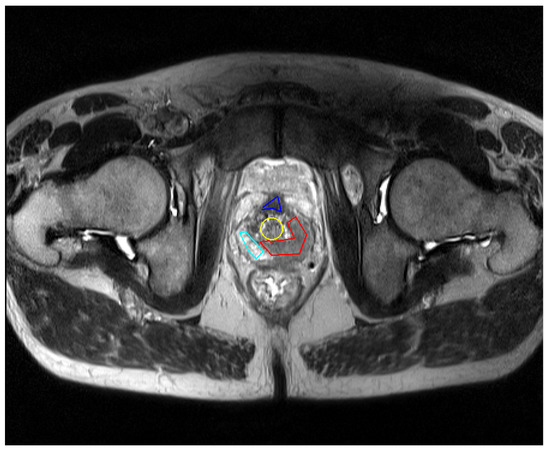

First, the user must load an image in DICOM format. For this application, the snake initialization is required; an example of the initial contours for a study is shown in Figure 8. In the area of the GUI that corresponds to the initialization of the snake, the three first buttons are used for selecting the different zones of the prostate, whereas the fourth one gives the possibility of selecting a tumor.

Located below these buttons, there are two radio buttons, enabling to choose the shape of the initial contour, which can be circular or manual. The first option corresponds to an initial contour with a shape of a circle whose radius can be specified with the spin box located at the end of this area. The possible values are between 1 and 30 pixels. The manual input enables the user to enter a random polygon as initial contour. If selected, the user just has to make a click with the mouse in the vertices of the desired polygon. There are no limits for the amount of points, or the shape of the polygon.

The steps required to initialize the snake for any of the prostate areas are the following:

• Select the type of contour to enter, circular or manual. In case of circular, enter also the radious.

• Select an area: TZ, PZ, CZ or Tumour.

• Create the initial contour for the snake in the left image. If it is a circle, the mouse cursor must be placed in the center of the area of interest, and click with the left button of the mouse. If manual contour has been chosen, the mouse must be placed in the point where the user wishes to start the contour and make click with the left button. Then move the cursor until the next point, make a left click and go to the next point. More than 2 points are required.

• In manual mode, once the contour is finished, press the “Ok” button. If not, go to step 5.

• A message box will appear informing if the contour has been correctly added or not.

The user can repeat the same procedure for all the zones, or just some of them. In order to differentiate the various selected areas, each initial contour will be drawn with a different color. There are no constraints about the type of contours to use. All the contours can be manual, all of them can be circles or they can be a combination of them.

Figure 8. Example of snake initialization for the four zones.